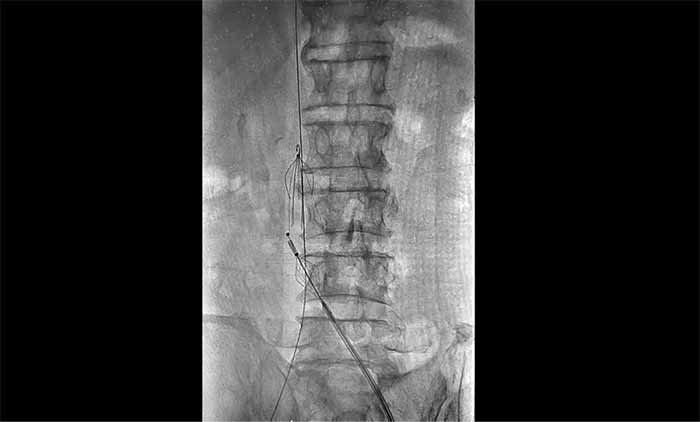

近日,上海藍(lán)十字腦科醫(yī)院腦血管病科收治了一名腦出血術(shù)后長(zhǎng)期臥床導(dǎo)致下肢深靜脈血栓形成的老年男性患者;颊咴谕庠嚎祻(fù)期間發(fā)現(xiàn)右下肢嚴(yán)重腫脹,超聲提示深靜脈血栓,緊急轉(zhuǎn)入本院。

席剛明教授與腦血管病一科4A病區(qū)副主任王貴平博士分析指出,下肢深靜脈血栓一旦脫落,可隨血流引發(fā)肺栓塞,危及生命?紤]到患者血栓形成時(shí)間較長(zhǎng)、抗凝效果不佳,團(tuán)隊(duì)決定行介入手術(shù)治療。術(shù)后造影顯示血栓基本消失,下肢靜脈恢復(fù)通暢,患者右下肢腫脹明顯緩解。

席教授提醒,即便置入濾器,仍需規(guī)范抗凝治療,以預(yù)防新血栓形成并降低脫落風(fēng)險(xiǎn)。